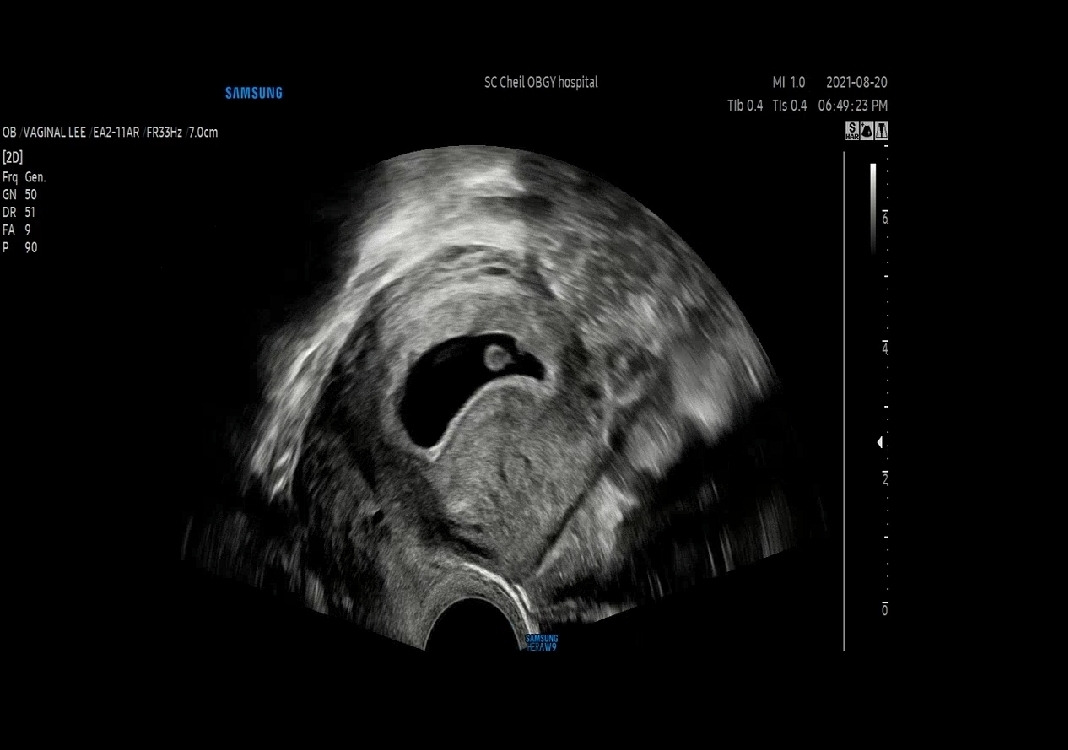

아가가 엄마 뱃속에 있었을 때가 있었어. 아가가 생긴 걸 알고 난 뒤, 처음 심장 소리를 들려준다고, 아가의 6주 차 2일에 SC제일산부인과(광진) 선생님이 초음파로 보여줬을 때 정말 감동이었어. 그냥 쿵쿵 120 정도 bpm의 소리 일뿐인데, 벅차오르는 느낌이 들어 신기했어. 눈물이 괜히 나려고 하고. 아가를 만나기 위한 설렘이라고 그랬던 것 같아.

초음파사진 캡쳐